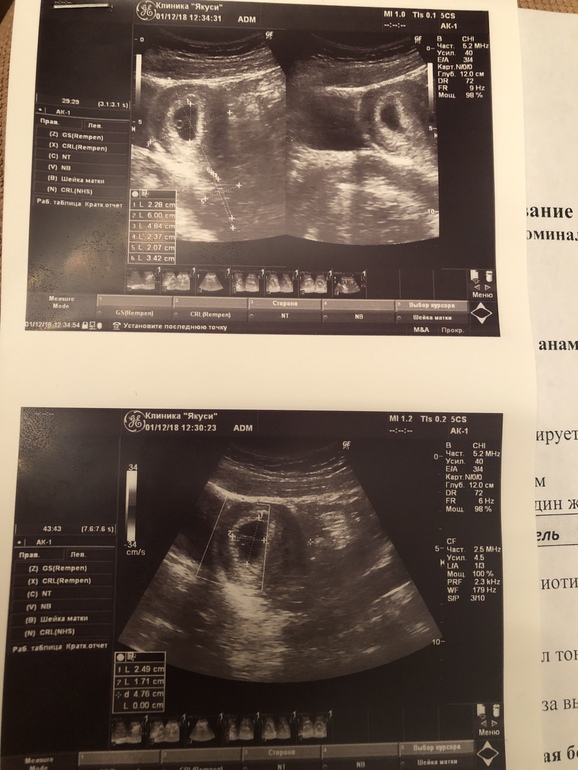

АнализыСегодня, предположительно, на 28 ДПО сходила на УЗИ, врач сказала, что все хорошо, никаких угроз нет.

У нас сердцебиение пока не услышали, у меня просто большая путаница с сроком из за того, что цикл совсем не регулярный и по месячным уже получается больше 8 недель, а овуляция предположительно была на 32 ДЦ, поэтому я не очень поняла срок 5 недель 4 дня это какой. Ещё мне делали не вагинальное узи, может это тоже на что-то влияет.

По узи все отлично у вас, поздравляю)

Я так понимаю, что 5+4 это эмбриональные, то есть около 7 акушерских, для этого срока много?